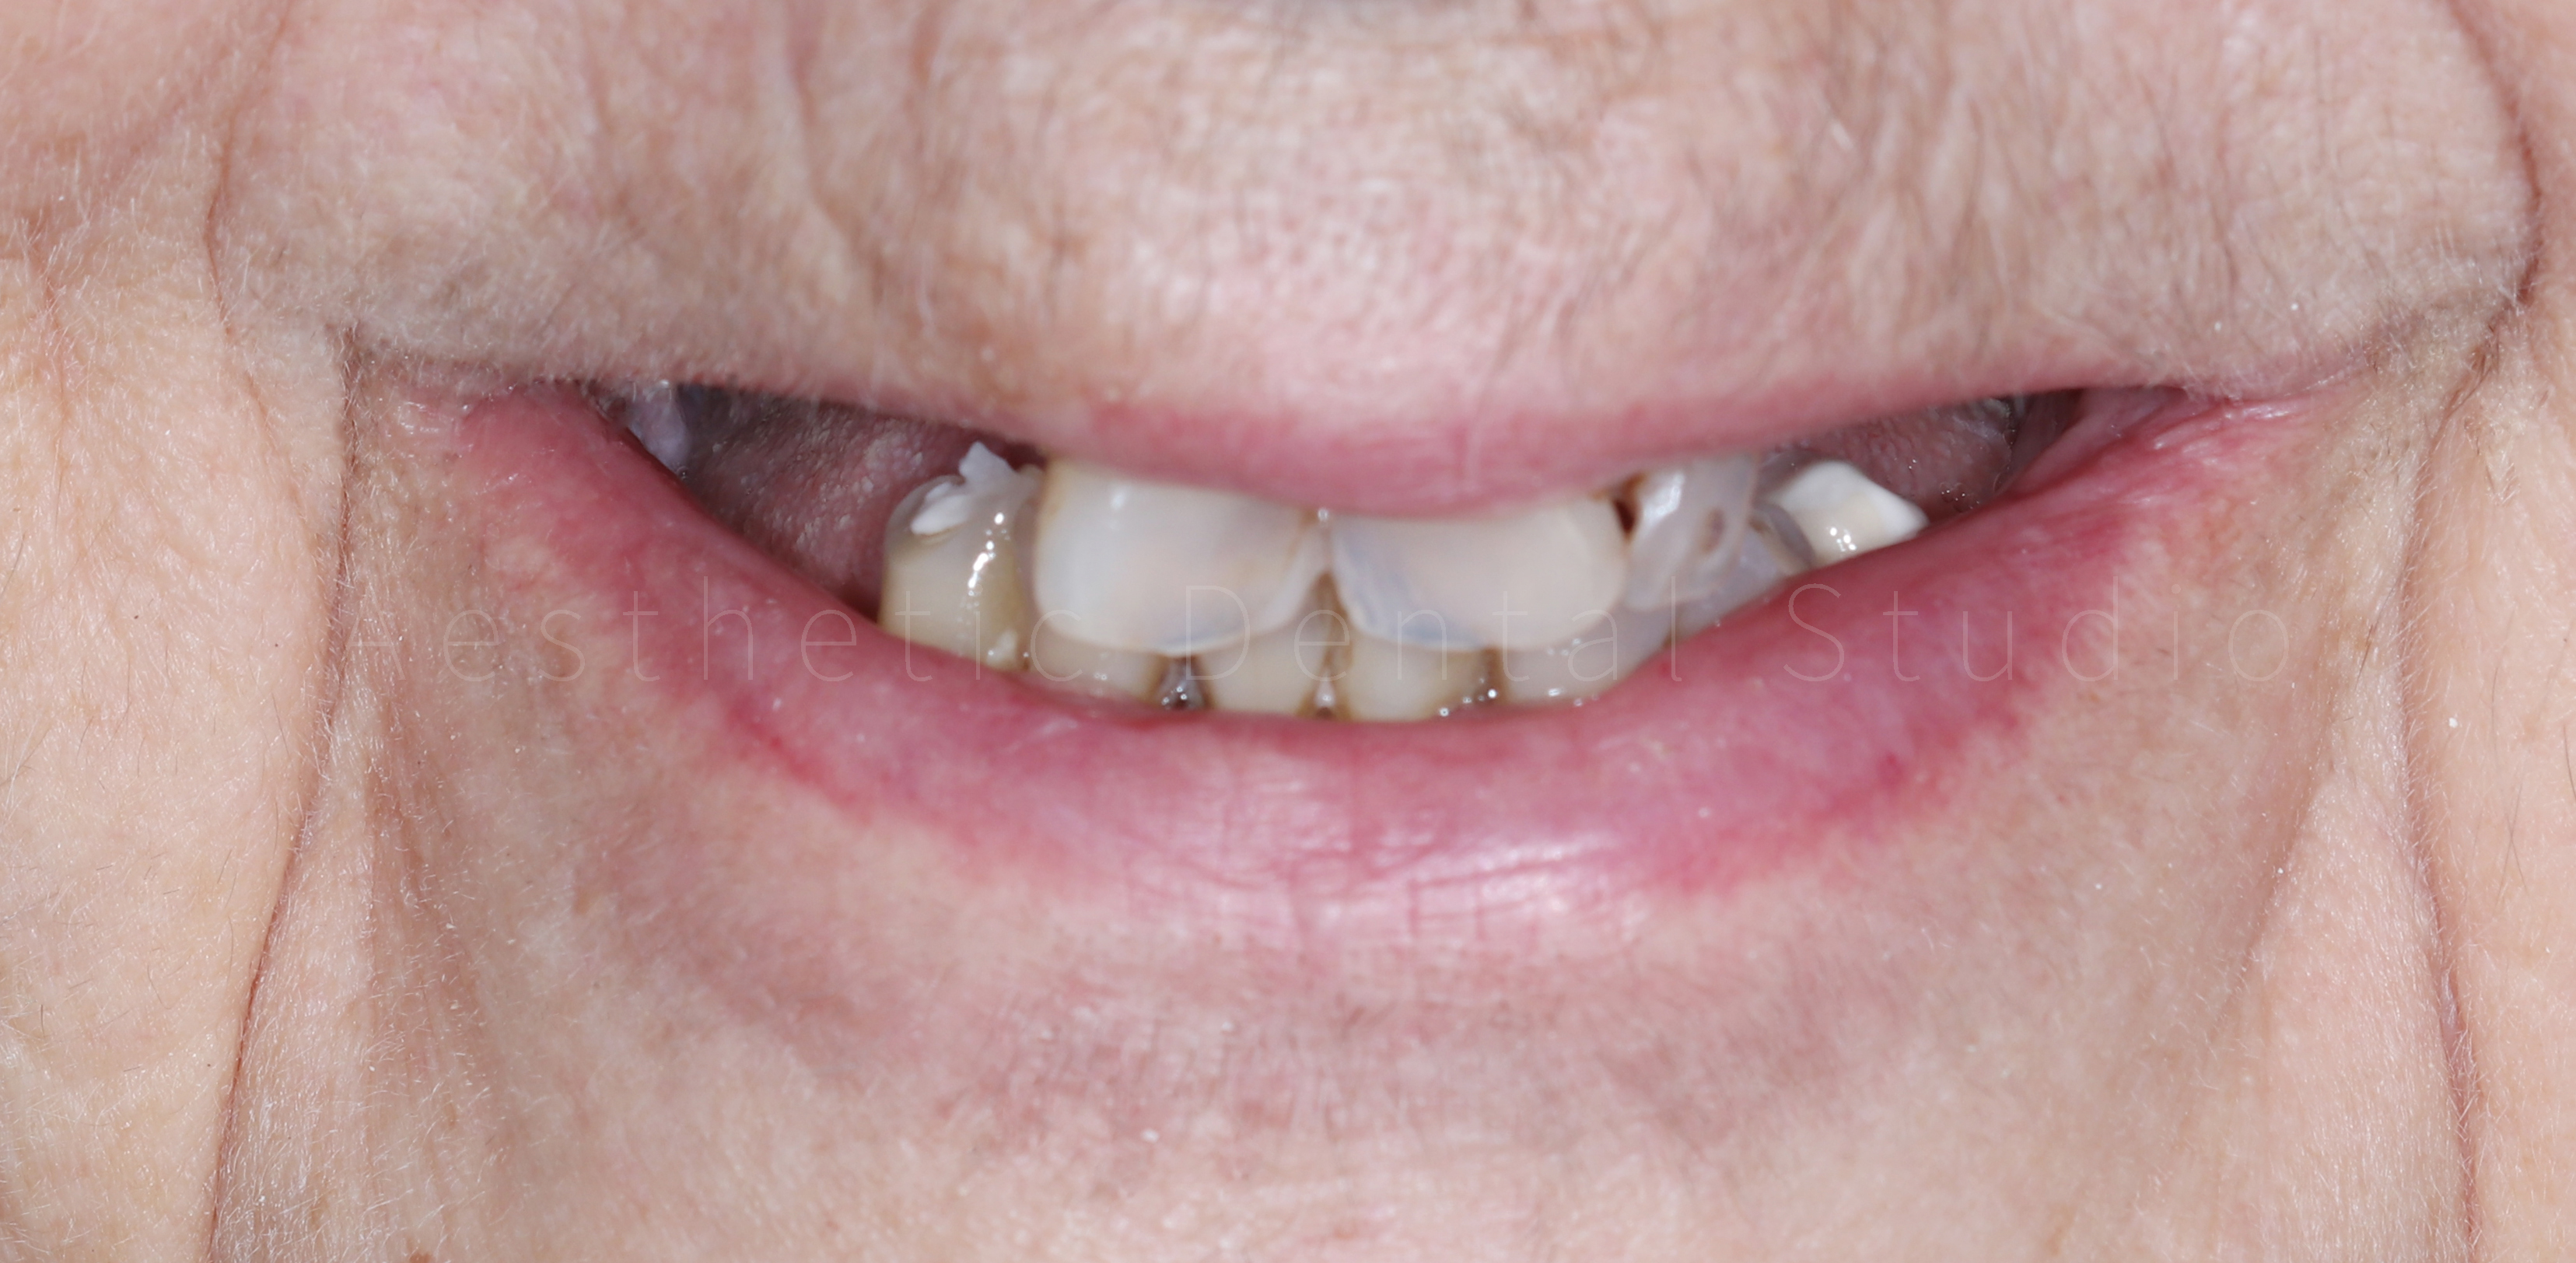

Ασθενής με εκτεταμένη φθορά και απώλεια δοντιών στην άνω και κάτω γνάθο προσήλθε στο Aesthetic Dental Studio στην Καλαμάτα με έντονη δυσκολία στη μάσηση, αισθητικά προβλήματα και επαναλαμβανόμενους πόνους. Η στοματική κατάσταση χαρακτηριζόταν από πολλαπλές τερηδόνες, κατεστραμμένα και ελλείποντα δόντια, γεγονός που επηρέαζε τόσο τη λειτουργία όσο και την αυτοπεποίθηση της ασθενούς.

Στην πρώτη φάση, πραγματοποιήθηκε πλήρης αποκατάσταση της στοματικής υγείας, με αφαίρεση των εναπομείναντων δοντιών της άνω γνάθου, αφού αυτά κρίθηκαν μη αποκαταστάσιμα. Παράλληλα διατηρήθηκαν τα κάτω πρόσθια δόντια και αποφασίστηκε η μετέπειτα προσθετική αποκατάστασή τους. Στην συνέχεια, ακολουθήθηκε χειρουργική τοποθέτηση εμφυτευμάτων σε στρατηγικές θέσεις με πλήρως ψηφιακό πρωτόκολλο: